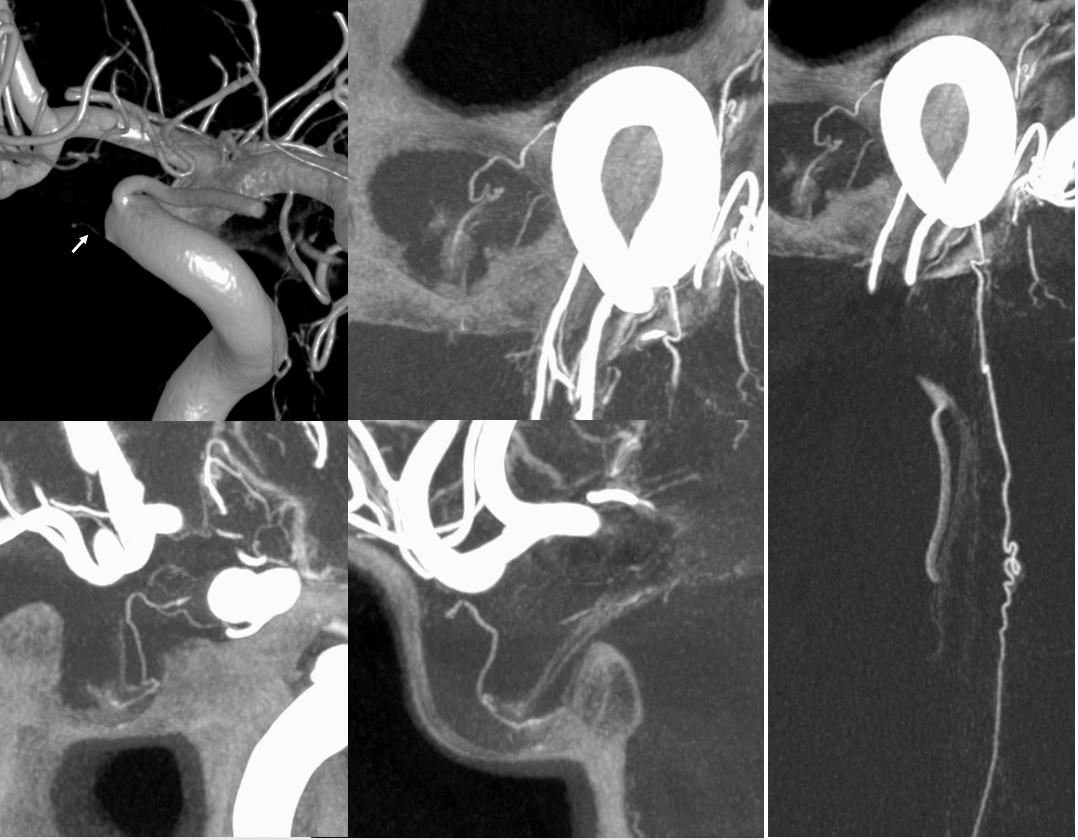

If you want to see hypophyseal arteries, do some high res DYNA of VASO imaging. Because of superimposition over the carotid in lateral views, again, its hard to see. Below is an example of why this artery, always there (always, yes! — occlusion is pathologic always such as athero) depends on technique

Stereos and MIPs. Both superior and inferior hypophyseals are well seen. The superior hypophyseal, despite being invisible on standard issue views, is quite large, even having two branches to the hypophysis.

Case courtesy Dr. Eytan Raz — here is a beautiful example of a very dominant superior hypophyseal artery (arrow) supplying the posterior hypophysis (arrowhead), with a correspondingly small inferior hypophyseal contribution from the MHT (dashed arrow)

Cross eye stereo

View from the back — again small inferior hypophyseal, big superior hypophyseal — balance again… See the beautiful vascular ring of the posterior pituitary — the connecting it with the contralateral side

Cross-eye stereo

MIP image shows the sella nicely — and helps prove its posterior pituitary

Pure arrowless images — easier to steal…

Of course, there is an aneurysm here — the branch point camp would point out how this larger than usual branch is a setup for aneurysmal formation. Naturally…

Below is a Volume Rendered typical arrangement — a slender (but still large by its own standards) superior hypophyseal supplies the stalk (and anterior pituitary), while inferior hypophyseal from MHT supply the posterior pituitary.

Sagittal MIP of the pituitary